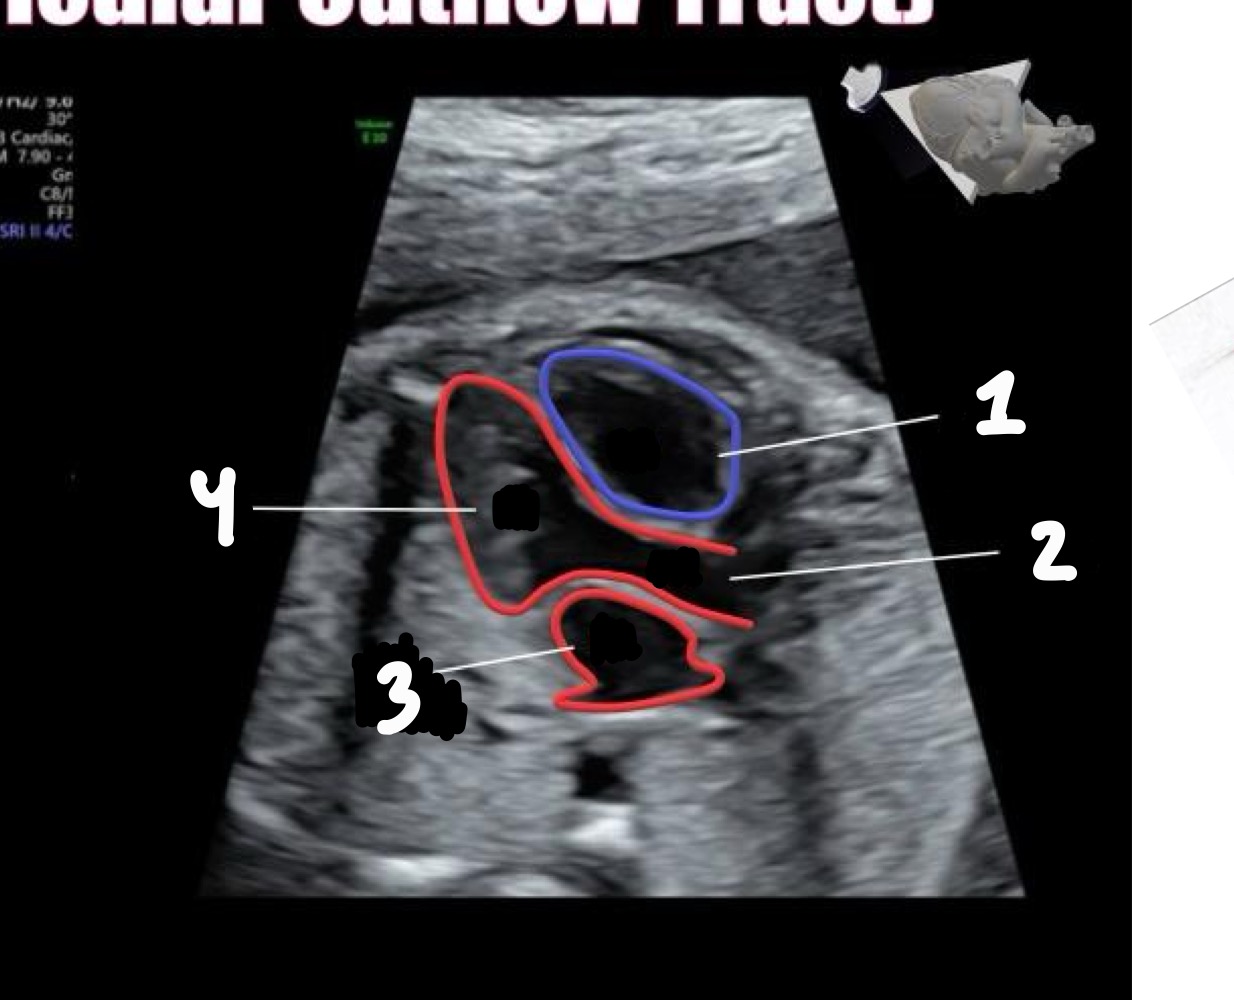

What does LVOT stand for

Left ventricular outflow tract

What vessel arises from the left ventricle in LVOT

Aorta

What is the "ballerina foot" sign associated with

LVOT view

What abnormality can be assessed in LVOT

Ventricular septal defect (VSD)

Right ventricle

Left atrium

Left ventricle